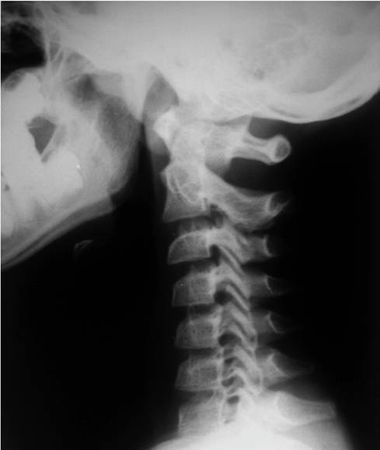

Рис. 4.4. Истинный травматический передний вывих CII у ребенка 16 лет. Линия Swischuk не нарушена (дуга CII не сломана). Имеется разобщение суставных поверхностей CII–CIII. Смещение CII кпереди и вниз на Vi тела CIII